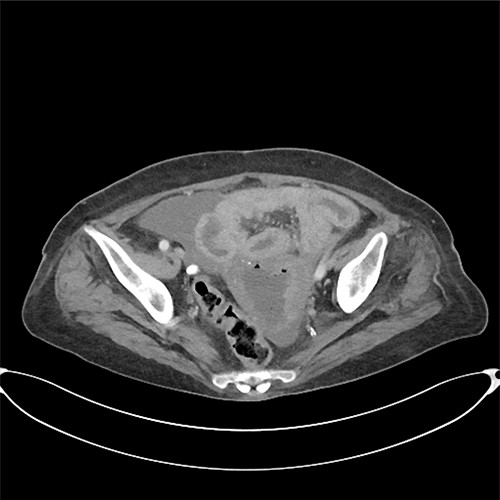

A computed tomography scan revealed significant abdominal ascites and scattered locules of intraperitoneal free air suggestive of a perforated viscous, although no clear gastrointestinal (GI) source was identified (Figs 1 and 2). In addition, evidence of pyometra with possible necrosis and intramural air within the uterine wall was identified. Emergent laparotomy was performed with complete exploration of the peritoneal cavity. The lesser sac was entered, and complete duodenal kocherization was performed, allowing for visualization of the entire GI tract. No GI perforation was identified. A 1-cm defect was seen on the fundus of the uterus with minimal ischaemic tissue surrounding the defect. Purulent material was seen to be emanating from the uterine cavity. The gynaecology service was consulted, and the uterus was assessed via intraoperative hysteroscopy with uterine lavage. Samples were sent for cytology, including uterine effluent and peritoneal fluid. In addition, uterine tissue at the borders of the defect were excised and sent for histopathologic review. All samples ultimately showed no evidence of malignancy.

Pneumoperitoneum demonstrated in the perihepatic and perigastric regions.